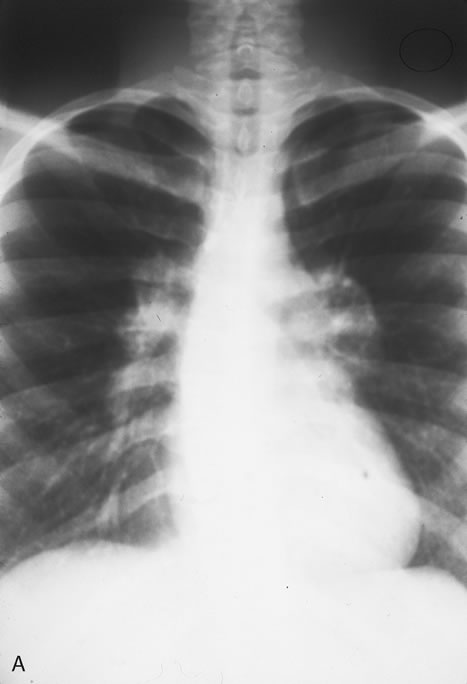

Pneumocystis carinii pneumonia once was the most common presentation of AIDS. It is typically of insidious onset, with features including dry cough, dyspnea, and a diffuse bilateral interstitial infiltrate evident on a chest roentgenogram. Typical multifocal fundus lesions have been described. They are yellow-white and have a characteristic pattern on fluorescein angiography (Fig. 10A, 10B, and 10C). Diagnosis is made by demonstrating the protozoon via sputum induction, bronchioalveolar lavage, and transbronchial or open-lung biopsies. Treatment modalities include trimethoprim-sulfamethoxazole (TMP-SMX).31